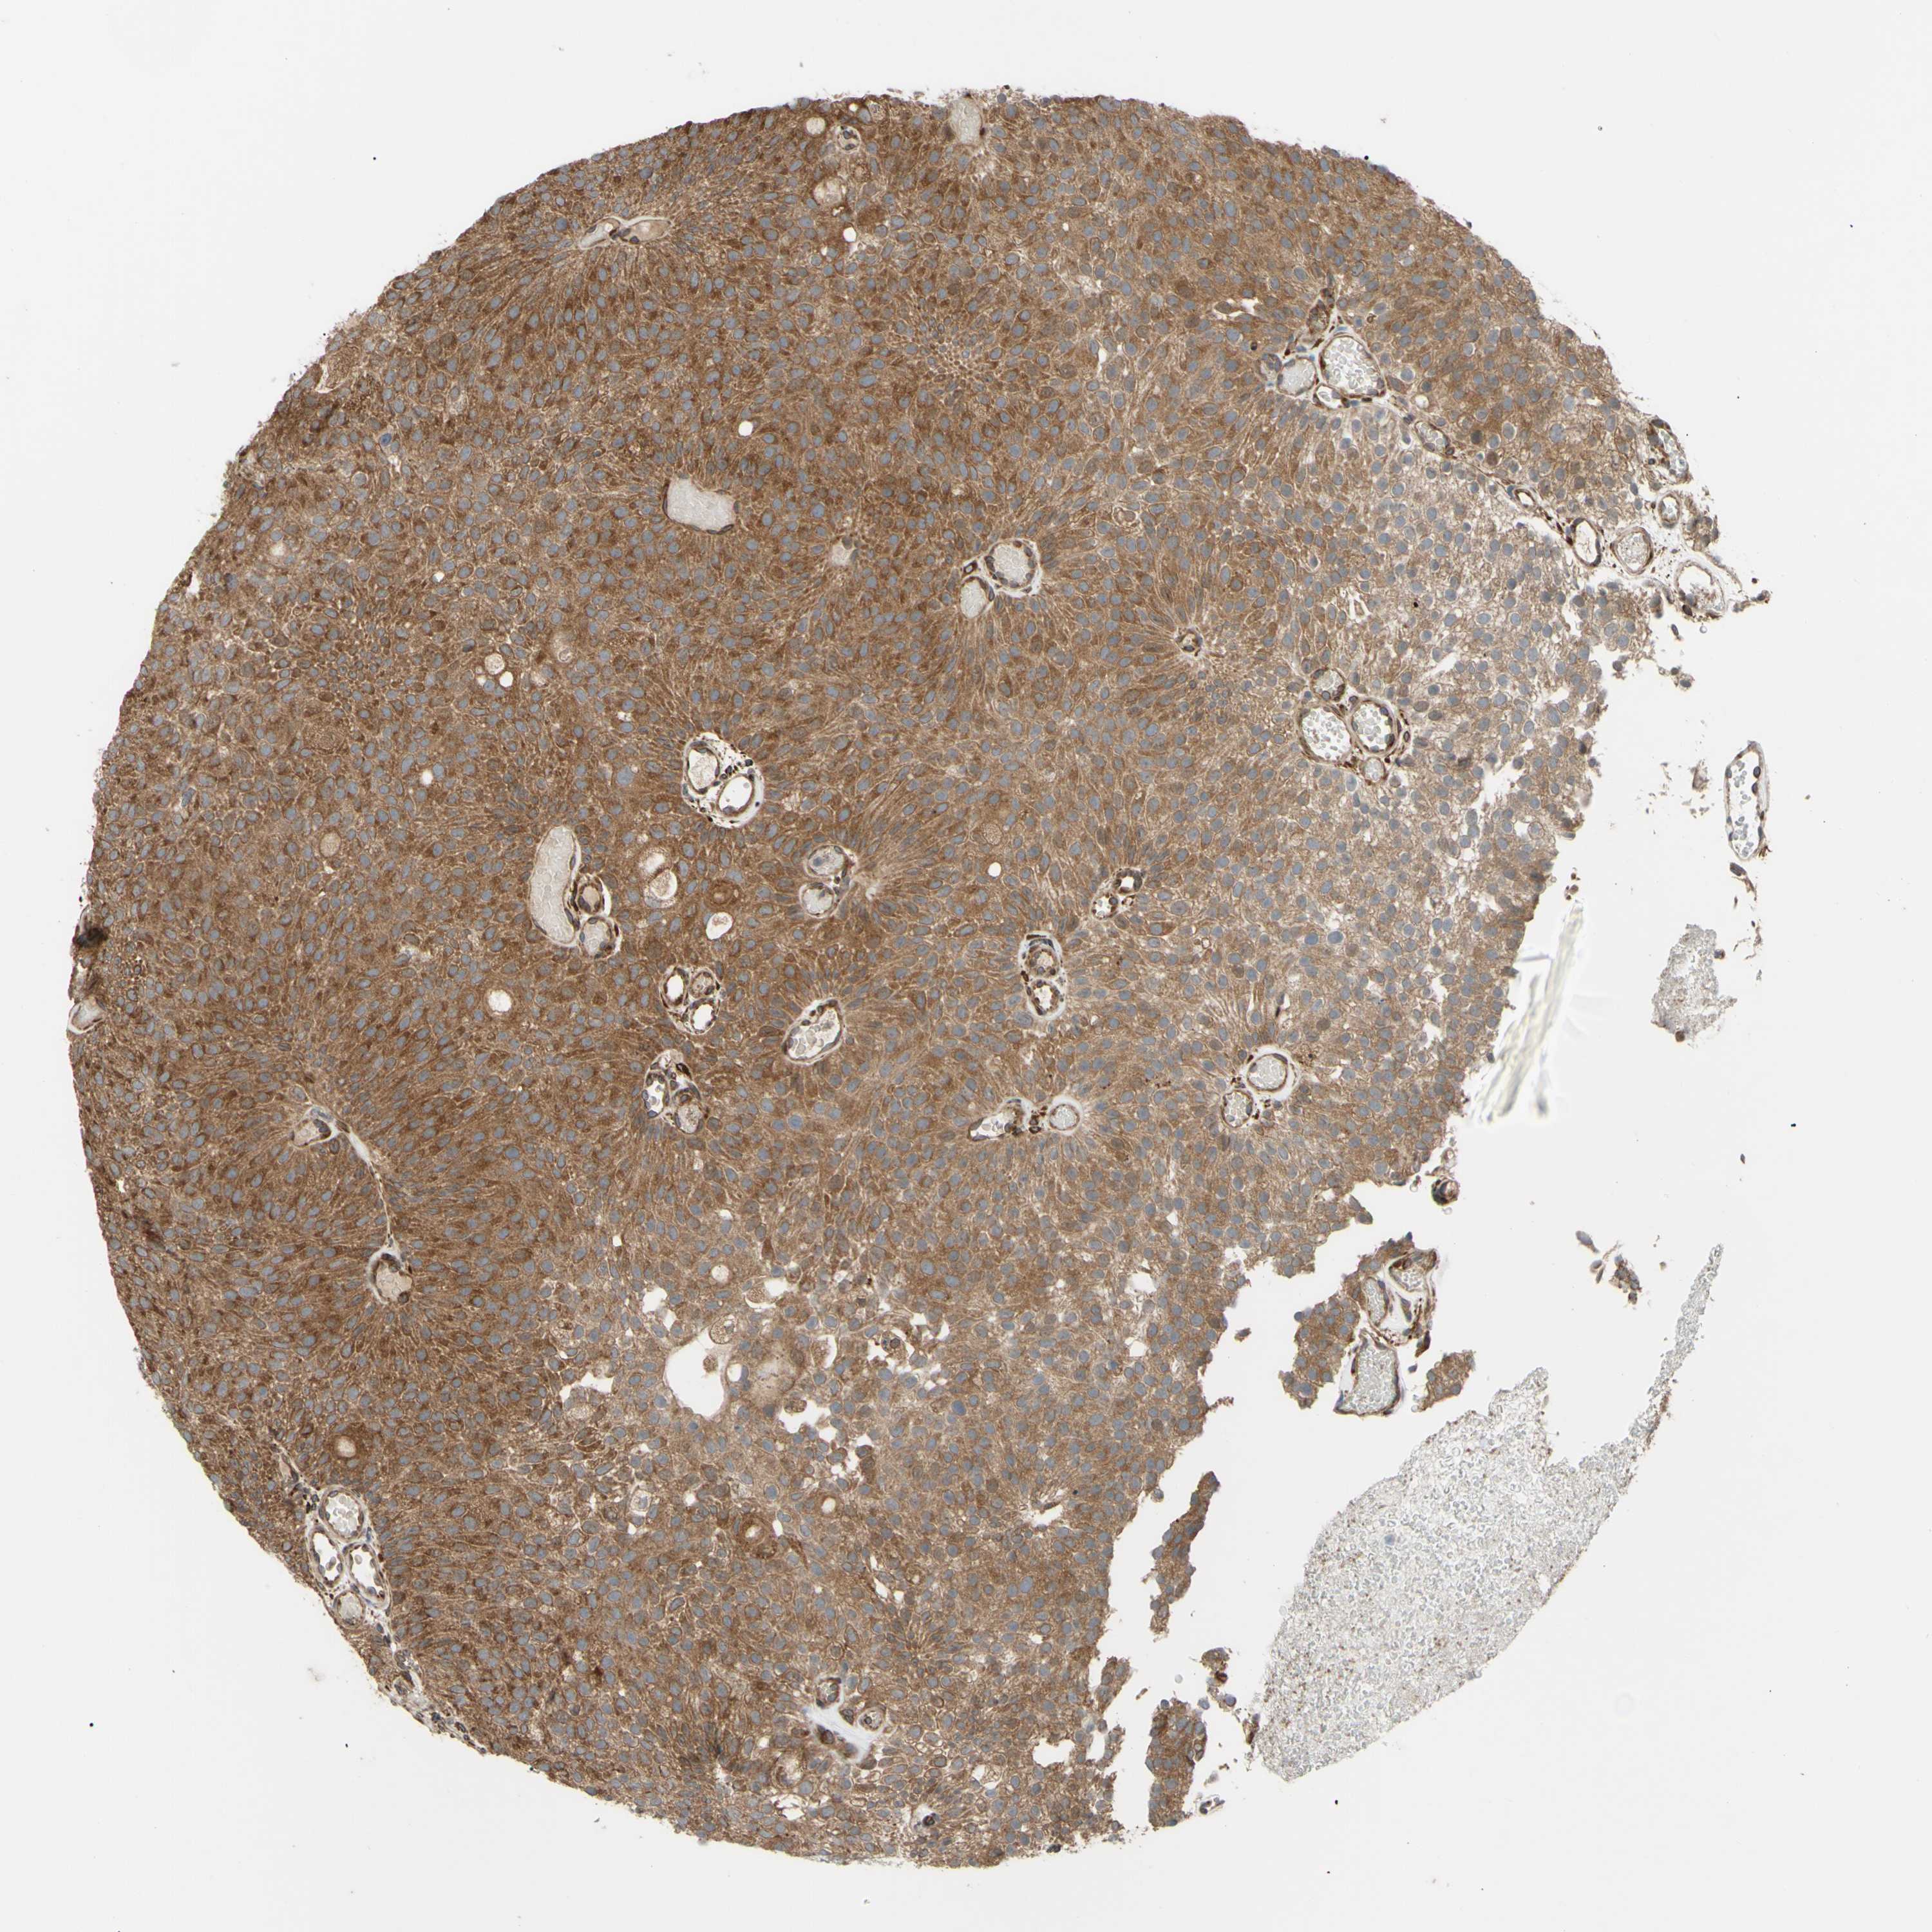

UROTHELIAL CANCER - Protein expressioni

A mouse-over function shows sample information and annotation data. Click on an image to view it in a full screen mode. Samples can be filtered based on level of antibody staining by selecting one or several of the following categories: high, medium, low and not detected. The assay and annotation is described here.

Antibody stainingi

Antibody staining in the annotated cell types in the current human tissue is reported as not detected, low, medium, or high, based on conventional immunohistochemistry profiling in selected tissues. This score is based on the combination of the staining intensity and fraction of stained cells.

Each image is clickable and will lead to virtual microscopy that enables deeper exploration of all samples and also displays staining intensity scores, fraction scores and subcellular localization as well as patient and tissue information for each sample.

Antibody HPA002859

Antibody CAB011655

Urothelial carcinoma, High grade

Urothelial carcinoma, Low grade

Adenocarcinoma, NOS